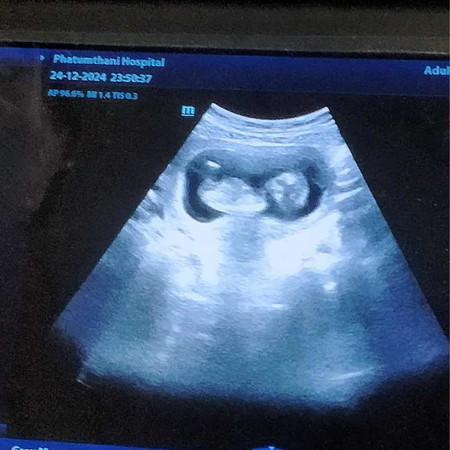

ขอสอบถามแม่ๆค่ะแบบนี้น้องแข็งแรงปลอดภัยใช่มั้ยคะพอดีโดนคนเมา ยาเอาไม้มาตีท้อง+คุณแม่มือใหม่ค่ะ+ ไม่ชาวตอน9w ค่ะ

การซาวด์ไม่ได้ดูความแข็งแรงหรือสิ่งผิดปกติของตัวเล็กนะเเม่ ลองสังเกตอาการตัวเองนะเเม่ มีเลือดออกไหม ปวดท้องไหม เเล้ว เเจ้งหมอด่วนค่ะ ให้หมอเช็คดูให้ระเอียดค่ะเเม่

หมอบอกไว้เสมอว่าการซาวด์ไม่สามารถดูสิ่งผิดปกติได้นะคะถ้ามีอาการแปลกๆไปหาหมอนะคะ